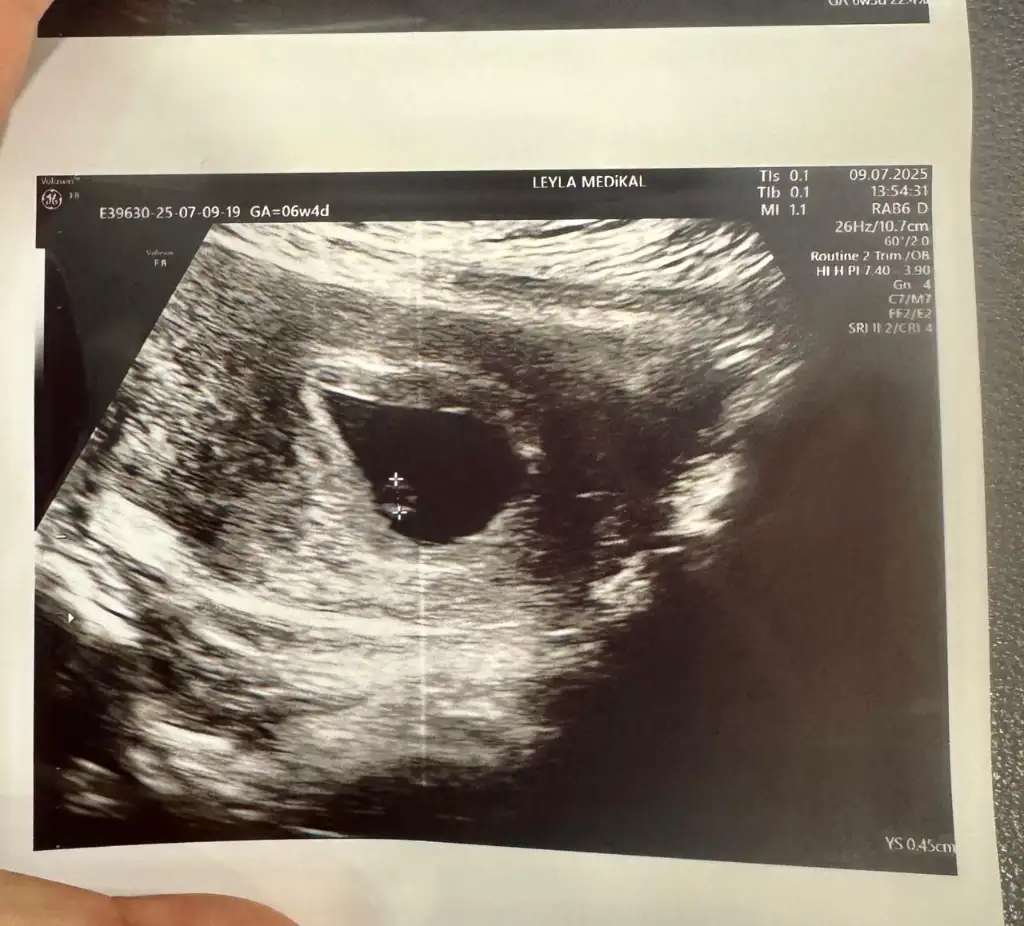

6 haftalik karından ultrasyon tahminde bulunabilir misiniz

Eklentiler

• IMG_20250312_112835.webp

IMG_20250312_112835.webp

31,3 KB · Görüntüleme: 70